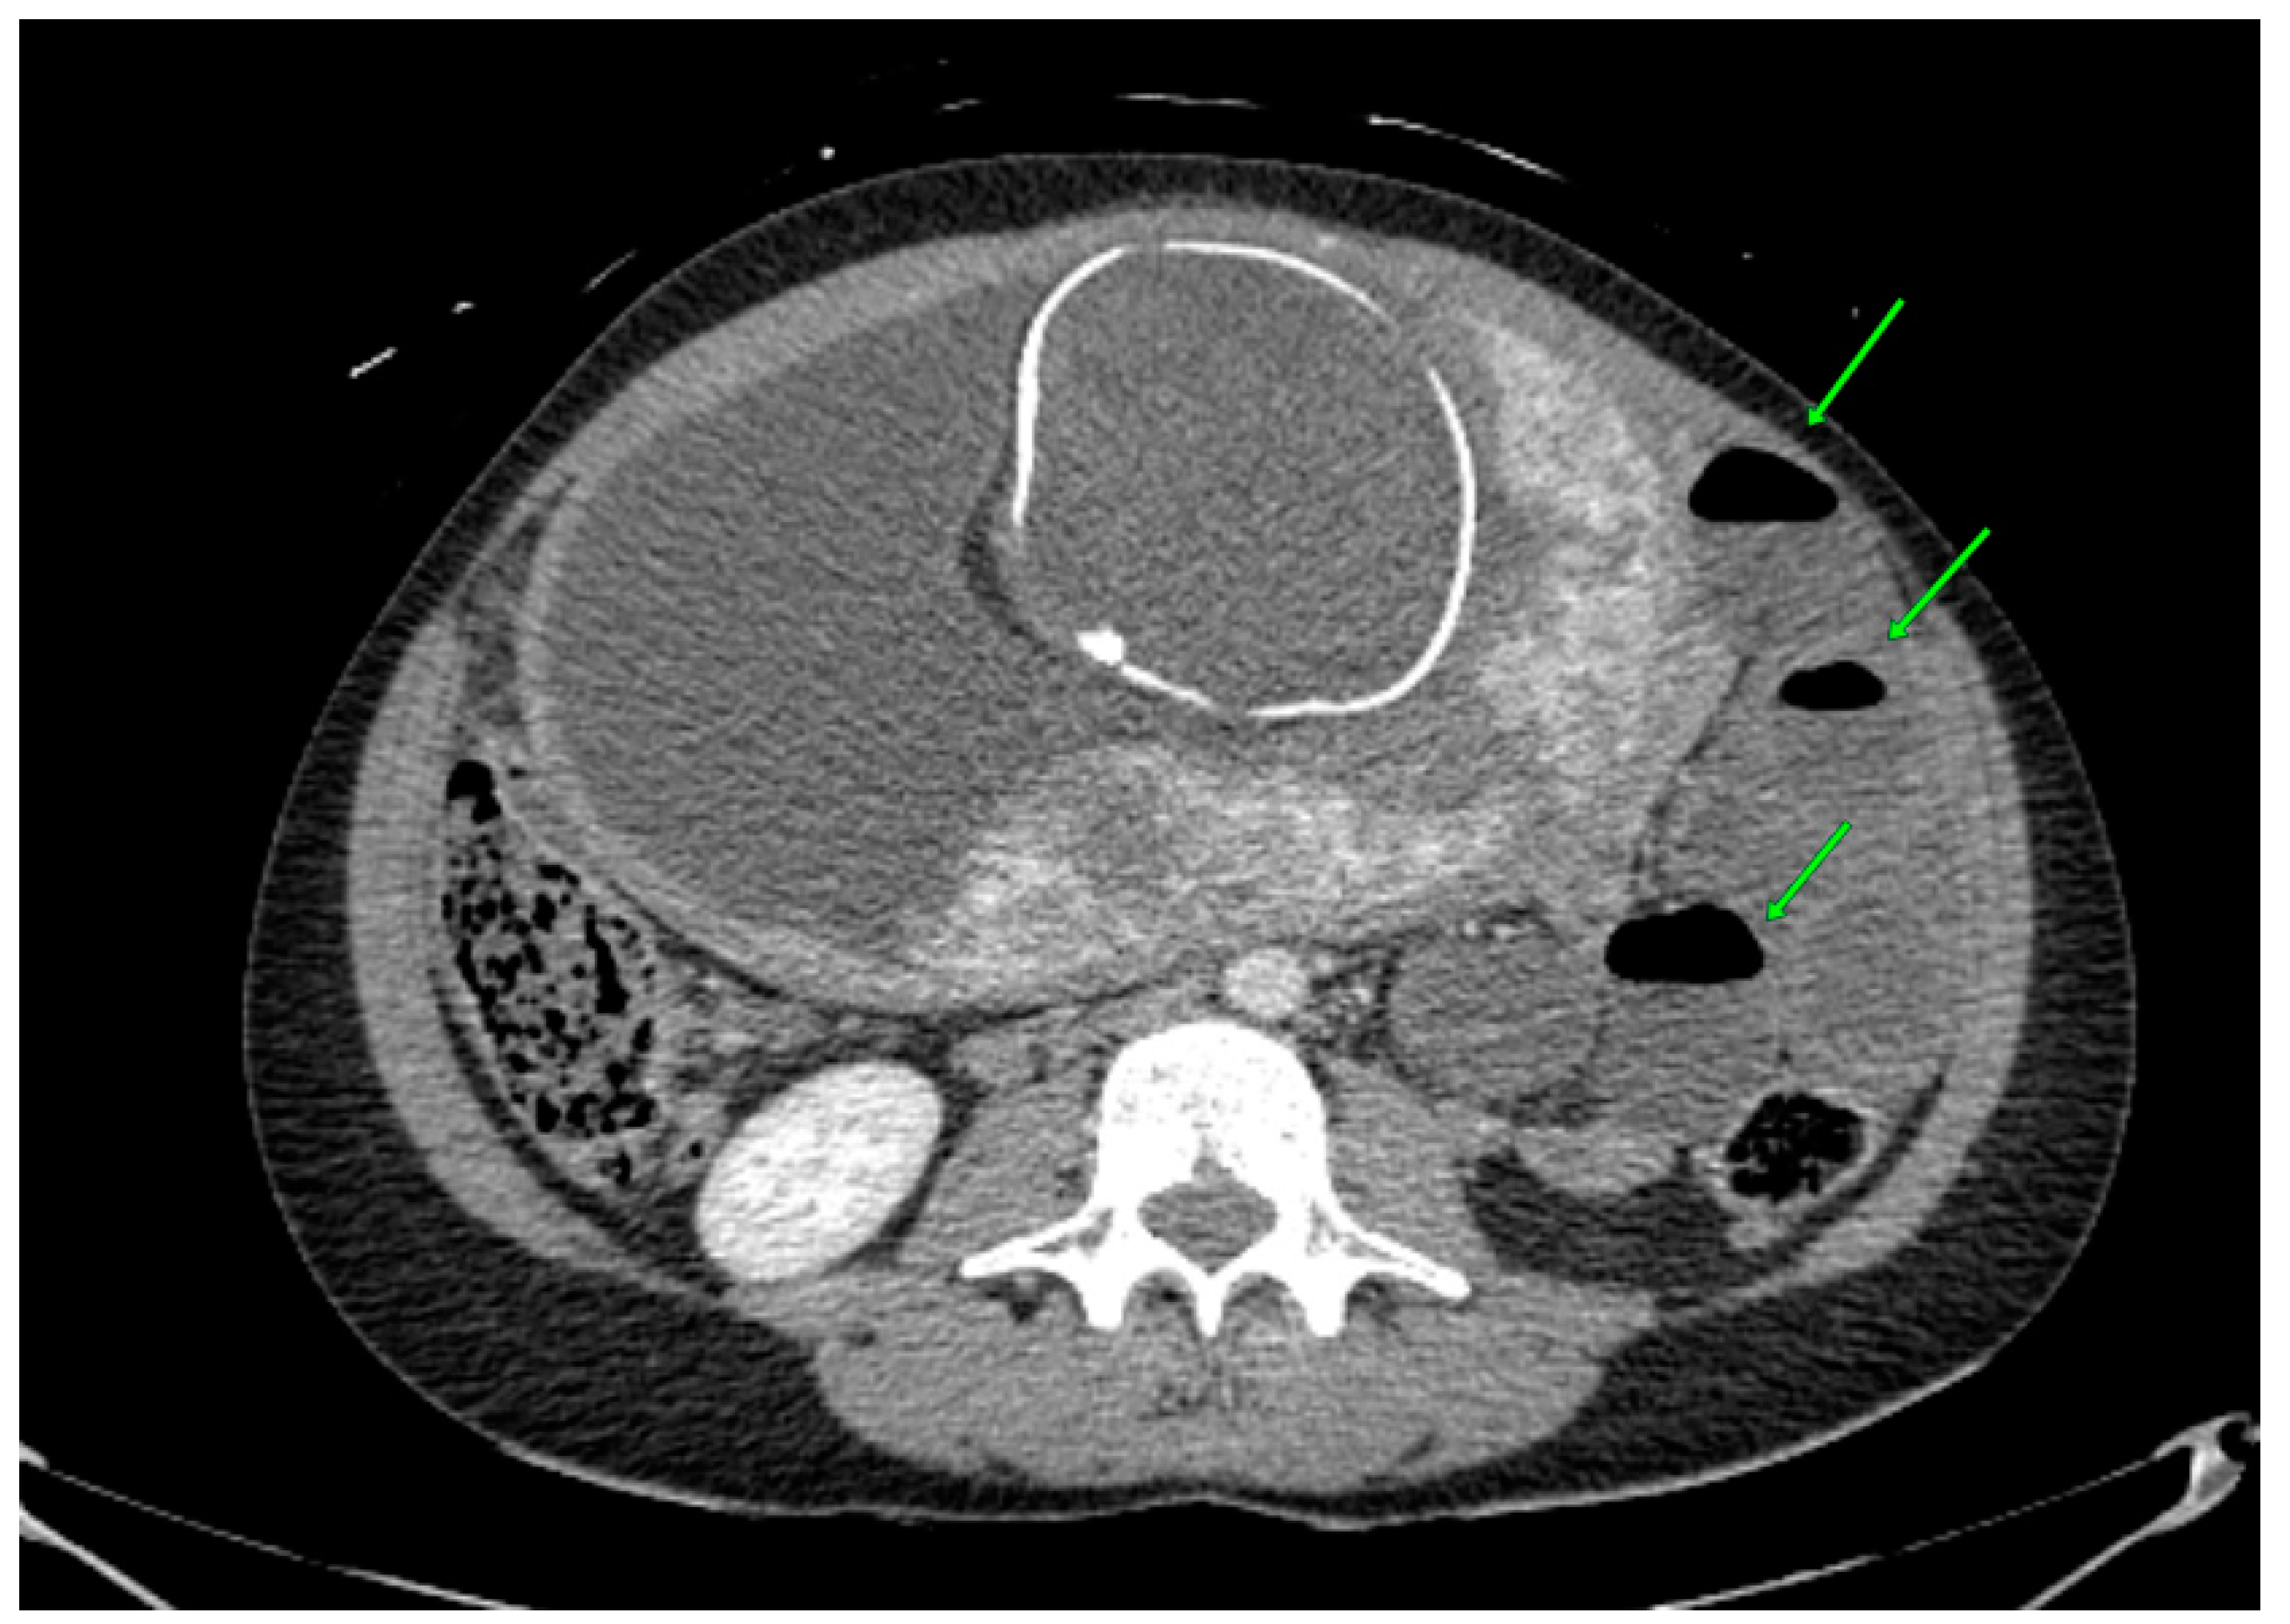

The abdominal CT revealed an obstruction in the small intestine due to a probable small bowel (ileo-pelvic) reversal. Two main symptoms, a dilated diameter of the small intestine (Figure 1) and air–fluid surfaces in the intestine, were found (Figure 2).

Figure 2. Abdomen CT findings. Air–fluid surfaces in the small intestine locally on the patient’s left—a symptom of bowel obstruction (green arrows).